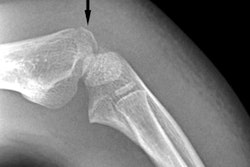

The effect of reconstruction field-of-view size on the displayed diameter of a nodule. Image courtesy of Samei et al.